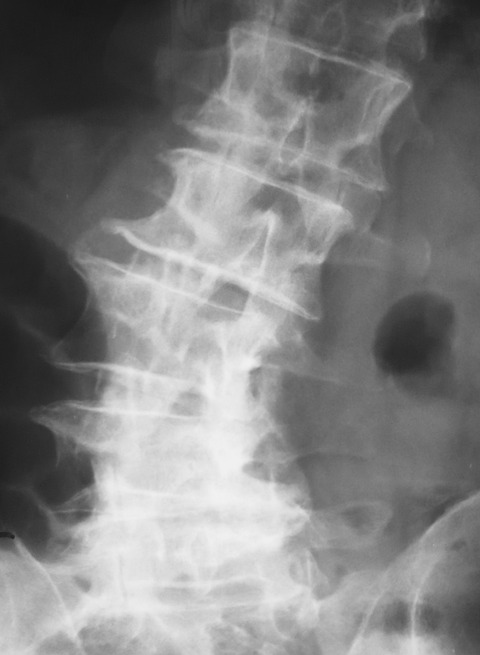

今回の除圧高位はL3/4に高度でしたが、変性側弯を認めました。

ご存知のように変性側弯では腰椎が回旋しているため、正中から掘削することが難しいです。

このような変性側弯症例では正確に正中から進入するため、術前のパイロット刺入の段階で手術台を傾けて腰椎の回旋変位を補正するようにしています。

補正前はこのような状態でした。L3/4の正中がどこか分かりにくいです。これでは正中から進入することが難しいので、イメージを見ながらL3の棘突起が中央にくるように手術台を傾けました。

少し分かりにくいですが、L3の棘突起が中央に位置しています。今回は左側を5度ほど下に傾けることで、このような状態に補正することができました。

このように手術台を傾けて腰椎の回旋の補正をすることで、変性側弯の手術といえども、通常の症例と同様に垂直方向に掘り下げて行くだけになります。

脊椎のエキスパートならこのようなお膳立ては不要かもしれません。しかし一般整形外科医の場合には、このような補正を加えるだけで普段通りの手術に早変わりします。